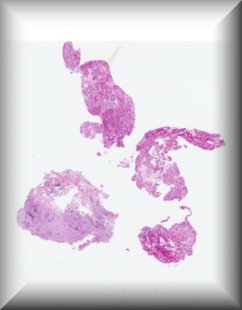

Sandra Lassalle (Guest): A 15 year old woman presenting with a left eye conjunctival pigmented lesion. The lesion has recently changed. Removal of the lesion has been approved. There is no particular clinical history. |